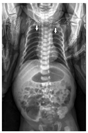

入院查体:体重3 160 g,面容特殊,嘴窄,神志清,弹足后哭声弱,呼吸促,呼吸频率62次/min,心脏查体无异常,无腹胀,无肝脾大,下肢肌张力正常,上肢肌张力减低,觅食、拥抱及握持反射不能引出。辅助检查:血常规:WBC 3.0×109/L,中性粒细胞绝对值0.5×109/L,红细胞2.3×1012/L,血红蛋白86 g/L,平均红细胞体积108 fL,血小板112×109/L;便常规未见脂肪球;肝功能:转氨酶正常;血淀粉酶7 U/L,脂肪酶4.5 U/L;免疫球蛋白定量及淋巴细胞绝对计数均正常。骨髓象增生重度减低。X线胸片可见胸廓较窄,后肋骨向下弯曲明显,呈弓状(图1);脊柱正位片未见异常,双下肢长骨干骺端未见明显异常。

骨骼发育异常在SDS中也比较常见,典型表现有身材矮小,可见于超过50%的病例;干骺端及软骨发育不良,可见于40%~80%的病例;胸廓发育不良,可见于30%~50%的病例,其中严重的胸廓畸形病例有新生儿期呼吸衰竭的病史[13];此外还有骨质疏松、锥体塌陷等表现。本例患儿X线胸片提示存在胸廓较窄,后肋骨向下弯曲呈弓形,符合SDS改变,长骨干骺端未见明显异常,复习文献发现国外SDS病例新生儿期较多存在胸廓发育不良,有13例(72.2%),15例(83.3%)存在骨干骺端发育异常等X线改变,既往有文献报道在新生儿期诊断为窒息性胸廓发育不良的病例最终确诊为SDS[14],但国内SDS存在骨骼发育异常的病例较少,没有胸廓发育不良的病例报道,可能因为国内医生对SDS的骨骼表现认识尚不足,需注意某些SDS病例可能在出生时即有胸廓窄、肋骨畸形等表现。